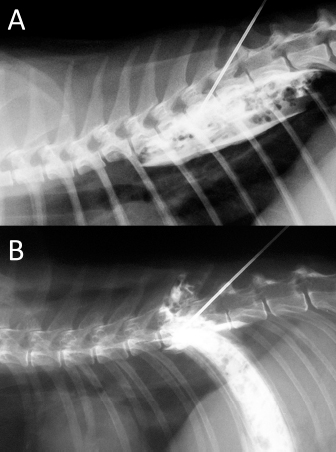

Fig. 3. Lateral spread of the polyurethane foam from the left cranial TPVS in a cat cadaver. At this level, the foam enters the axillary space, completely surrounding the axillary artery and the visible proximal branches of the brachial plexus (arrow). (A) ventral view. (B) left lateral view.

Three-directional spread (cranial, lateral, and caudal) from the probe tip at the level of the first costovertebral joint was observed. At the level of the thoracic inlet, the foam had spread between the parietal pleura, the endothoracic fascia, and the longus colli muscles, in contact with the cervicothoracic ganglion and the sympathetic trunk. From this level, it then spread cranially, dorsally surrounding the left subclavian artery, and distributing within the connective tissue dorsolateral to the trachea between (and in contact with) the longus colli muscles, the trachea, the sympathetic trunk, the common carotid artery, and the esophagus. The foam was also noted to spread laterally, following the subclavian artery over the first rib, and enter the axillary space, completely surrounding the axillary artery and the visible proximal branches of the brachial plexus (Fig. 3). Caudally, the foam spread ventral to the TPVS between the parietal pleura, the endothoracic fascia, and the longus colli muscles, where it came into contact with the sympathetic trunk, the rami communicantes, and the dorsal intercostal arteries. The foam also spread ventrally, dorsal to the large blood vessels of the dorsal mediastinum. Cranial and caudal spread of the foam was observed from the probe tip at the level of the last costovertebral joint. The cranial spread at this level was identical to the aforementioned caudal spread from the cranial injection, whereas caudally it varied across subjects. The foam spread was limited to the lumbo-costal arch of the diaphragm in 3/5 dogs and 4/5 cats, while in 2/5 dogs and 1/5 cats it extended past this point, distributing through the arch between the transversalis fascia and the psoas minor muscle between the quadratus lumborum and the minor psoas muscles (Figs. 4 and 5). In one dog, it spread even more caudally, between the major and the minor psoas muscles to the level of the sacral region.